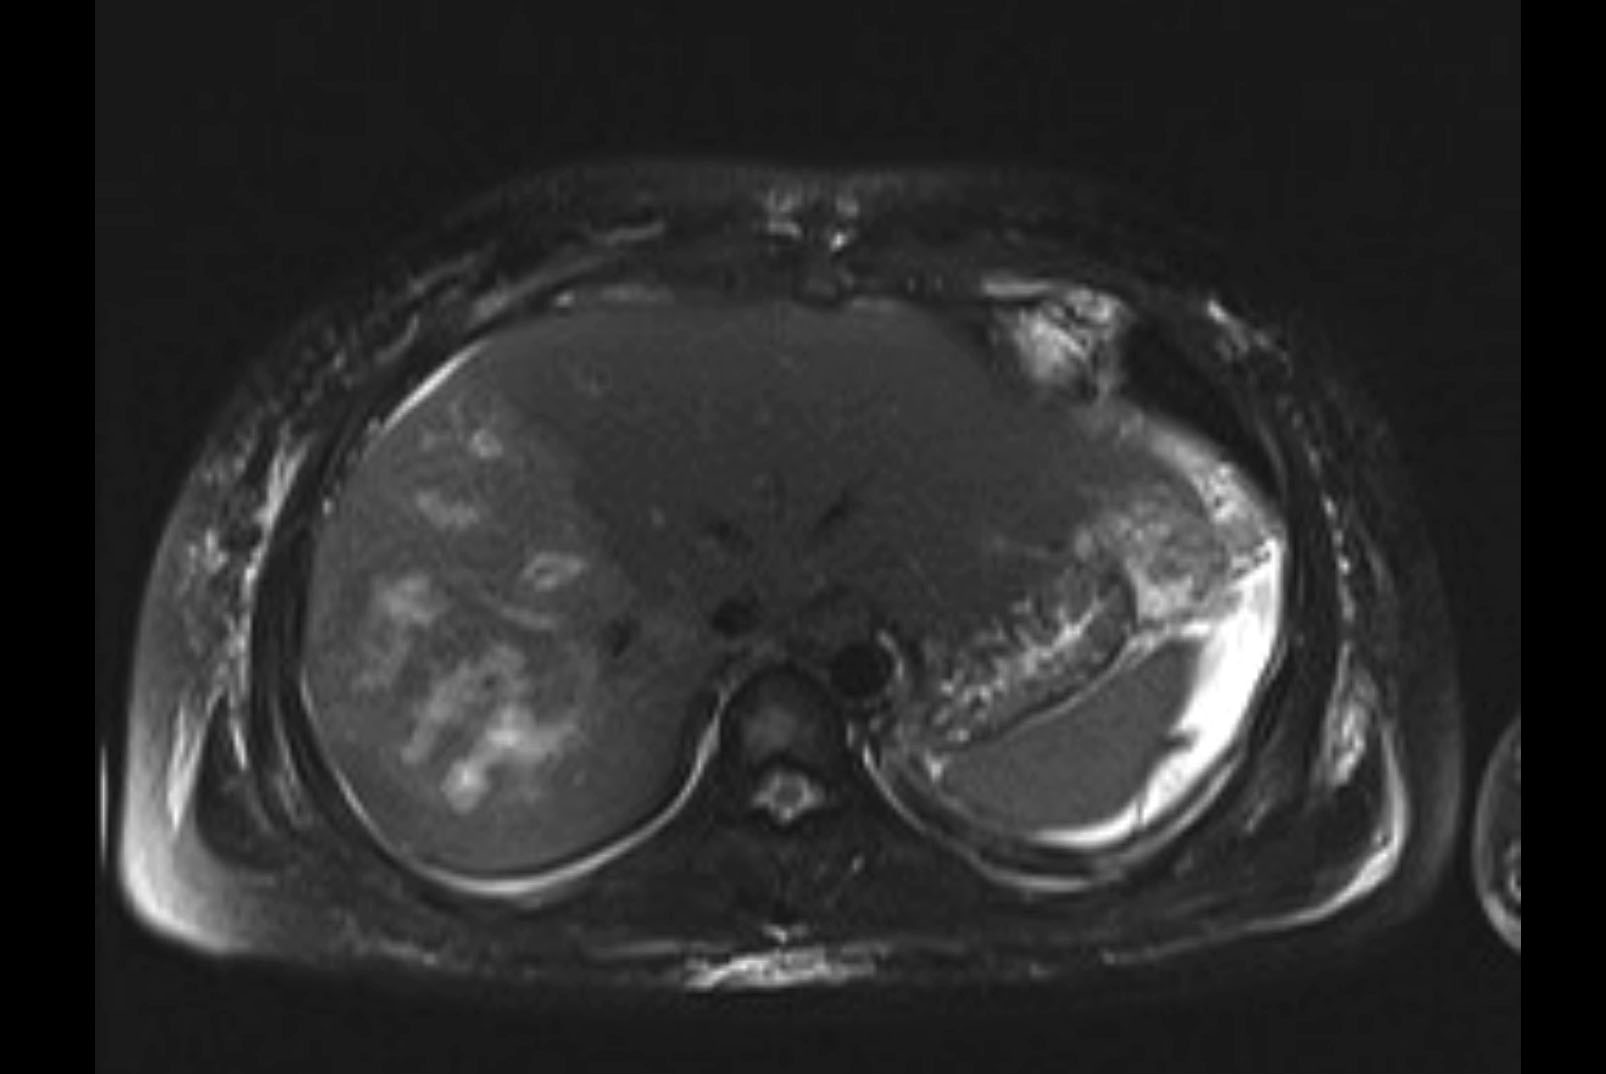

MRI T1

MRI T2